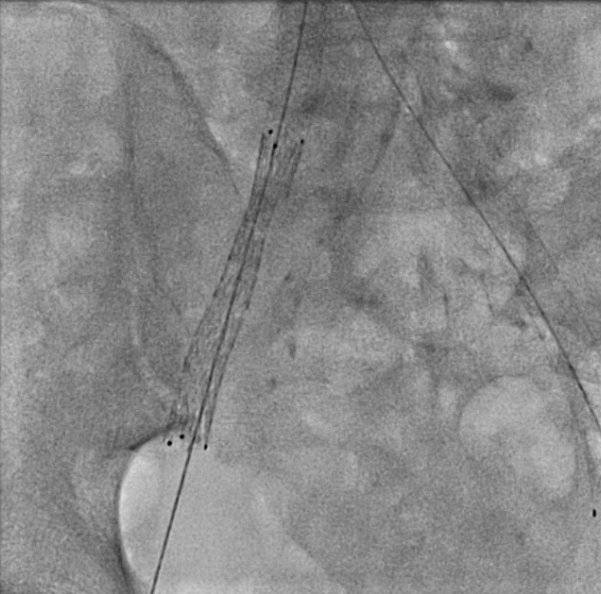

Venography showed occlusion of the right external and common iliac veins with collateral flow; popliteal and femoral veins were patent. A 6F sheath was placed in the right CFV, and a V-18 0.018 wire was advanced to the IVC. Attempts to traverse outside the prior left iliac-femoral stent for double-barrel reconstruction were unsuccessful, as the wire repeatedly entered the existing stent, likely due to complete apposition.The strategy was revised, and wiring into the IVC through a proximal stent strut was achieved. IVUS from the IVC to the RCFV confirmed severe compression at the right CIV ostium and proper wire position. A 10 ¡¿ 39 mm Abbott Omnilink balloon-expandable stent was deployed at the RCIV ostium and dilated to 10 atm. A kissing-balloon angioplasty was then performed with a 12 ¡¿ 40 mm Armada balloon from the LCIV and the RCIV balloon inflated simultaneously to 10 atm, restoring bifurcation geometry.A 14 ¡¿ 60 mm Bard Venovo stent was placed from the RCIV to the REIV and post-dilated with a 12 mm balloon to 10 atm. Final angiography showed widely patent, well-expanded stents with brisk antegrade flow into the IVC and no residual stenosis or thrombosis. Hemostasis was achieved with manual compression, and the procedure concluded without complications.